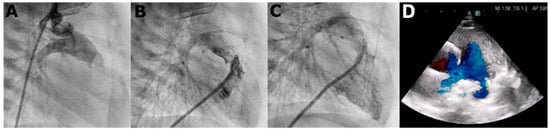

We report a 4-year-old boy with a history that includes a prenatal diagnosis of PA-IVS (International Paediatric and Congenital Cardiac Code 01.01.07) [] with confluent pulmonary branches. He underwent neonatal percutaneous pulmonary valvulotomy (Figure 1) with no significant RVOT gradient. No signs of coronary abnormalities were found. During follow-up, he presented signs of neurodevelopmental delay with autistic traits. For this reason, a genetic analysis through an exome TRIO identified a rare nonsense de novo variant in SCN5A gene (c.1603C>T, p.Arg535Ter) in heterozygosis, previously reported in patients with BrS and classified as pathogenic. Consequently, he was referred to our pediatric arrhythmia center, the reference center for rare inherited cardiac diseases. The basal ECG (Figure 2) presented sinus rhythm, PR of 154 ms, QRS duration of 88 ms, negative T waves in precordial leads V1–V4, and no Brugada ECG pattern, neither in standard nor in high precordial lead placement. The echocardiogram (ECHO) showed a dilated right atrium, moderate tricuspid regurgitation, right ventricle hypertrophy and mild dilation, and moderate pulmonary regurgitation, with no significant RVOT residual gradient nor additional vascular malformations such as aorto-pulmonary collaterals. No signs of coronary abnormalities were found during the neonatal catheterization.

Figure 1.

Angiography performed at the neonatal period showing: retrograde injection through the aorta showing pulmonary atresia (panel A), anterograde injection at the right ventricle outflow tract after perforation of the pulmonary valve (panel B), and final anterograde injection of the right ventricle after the final valvuloplasty (panel C). Echocardiography at 4 years-old showing the right ventricle outflow tract with the pulmonary arteries (panel D).